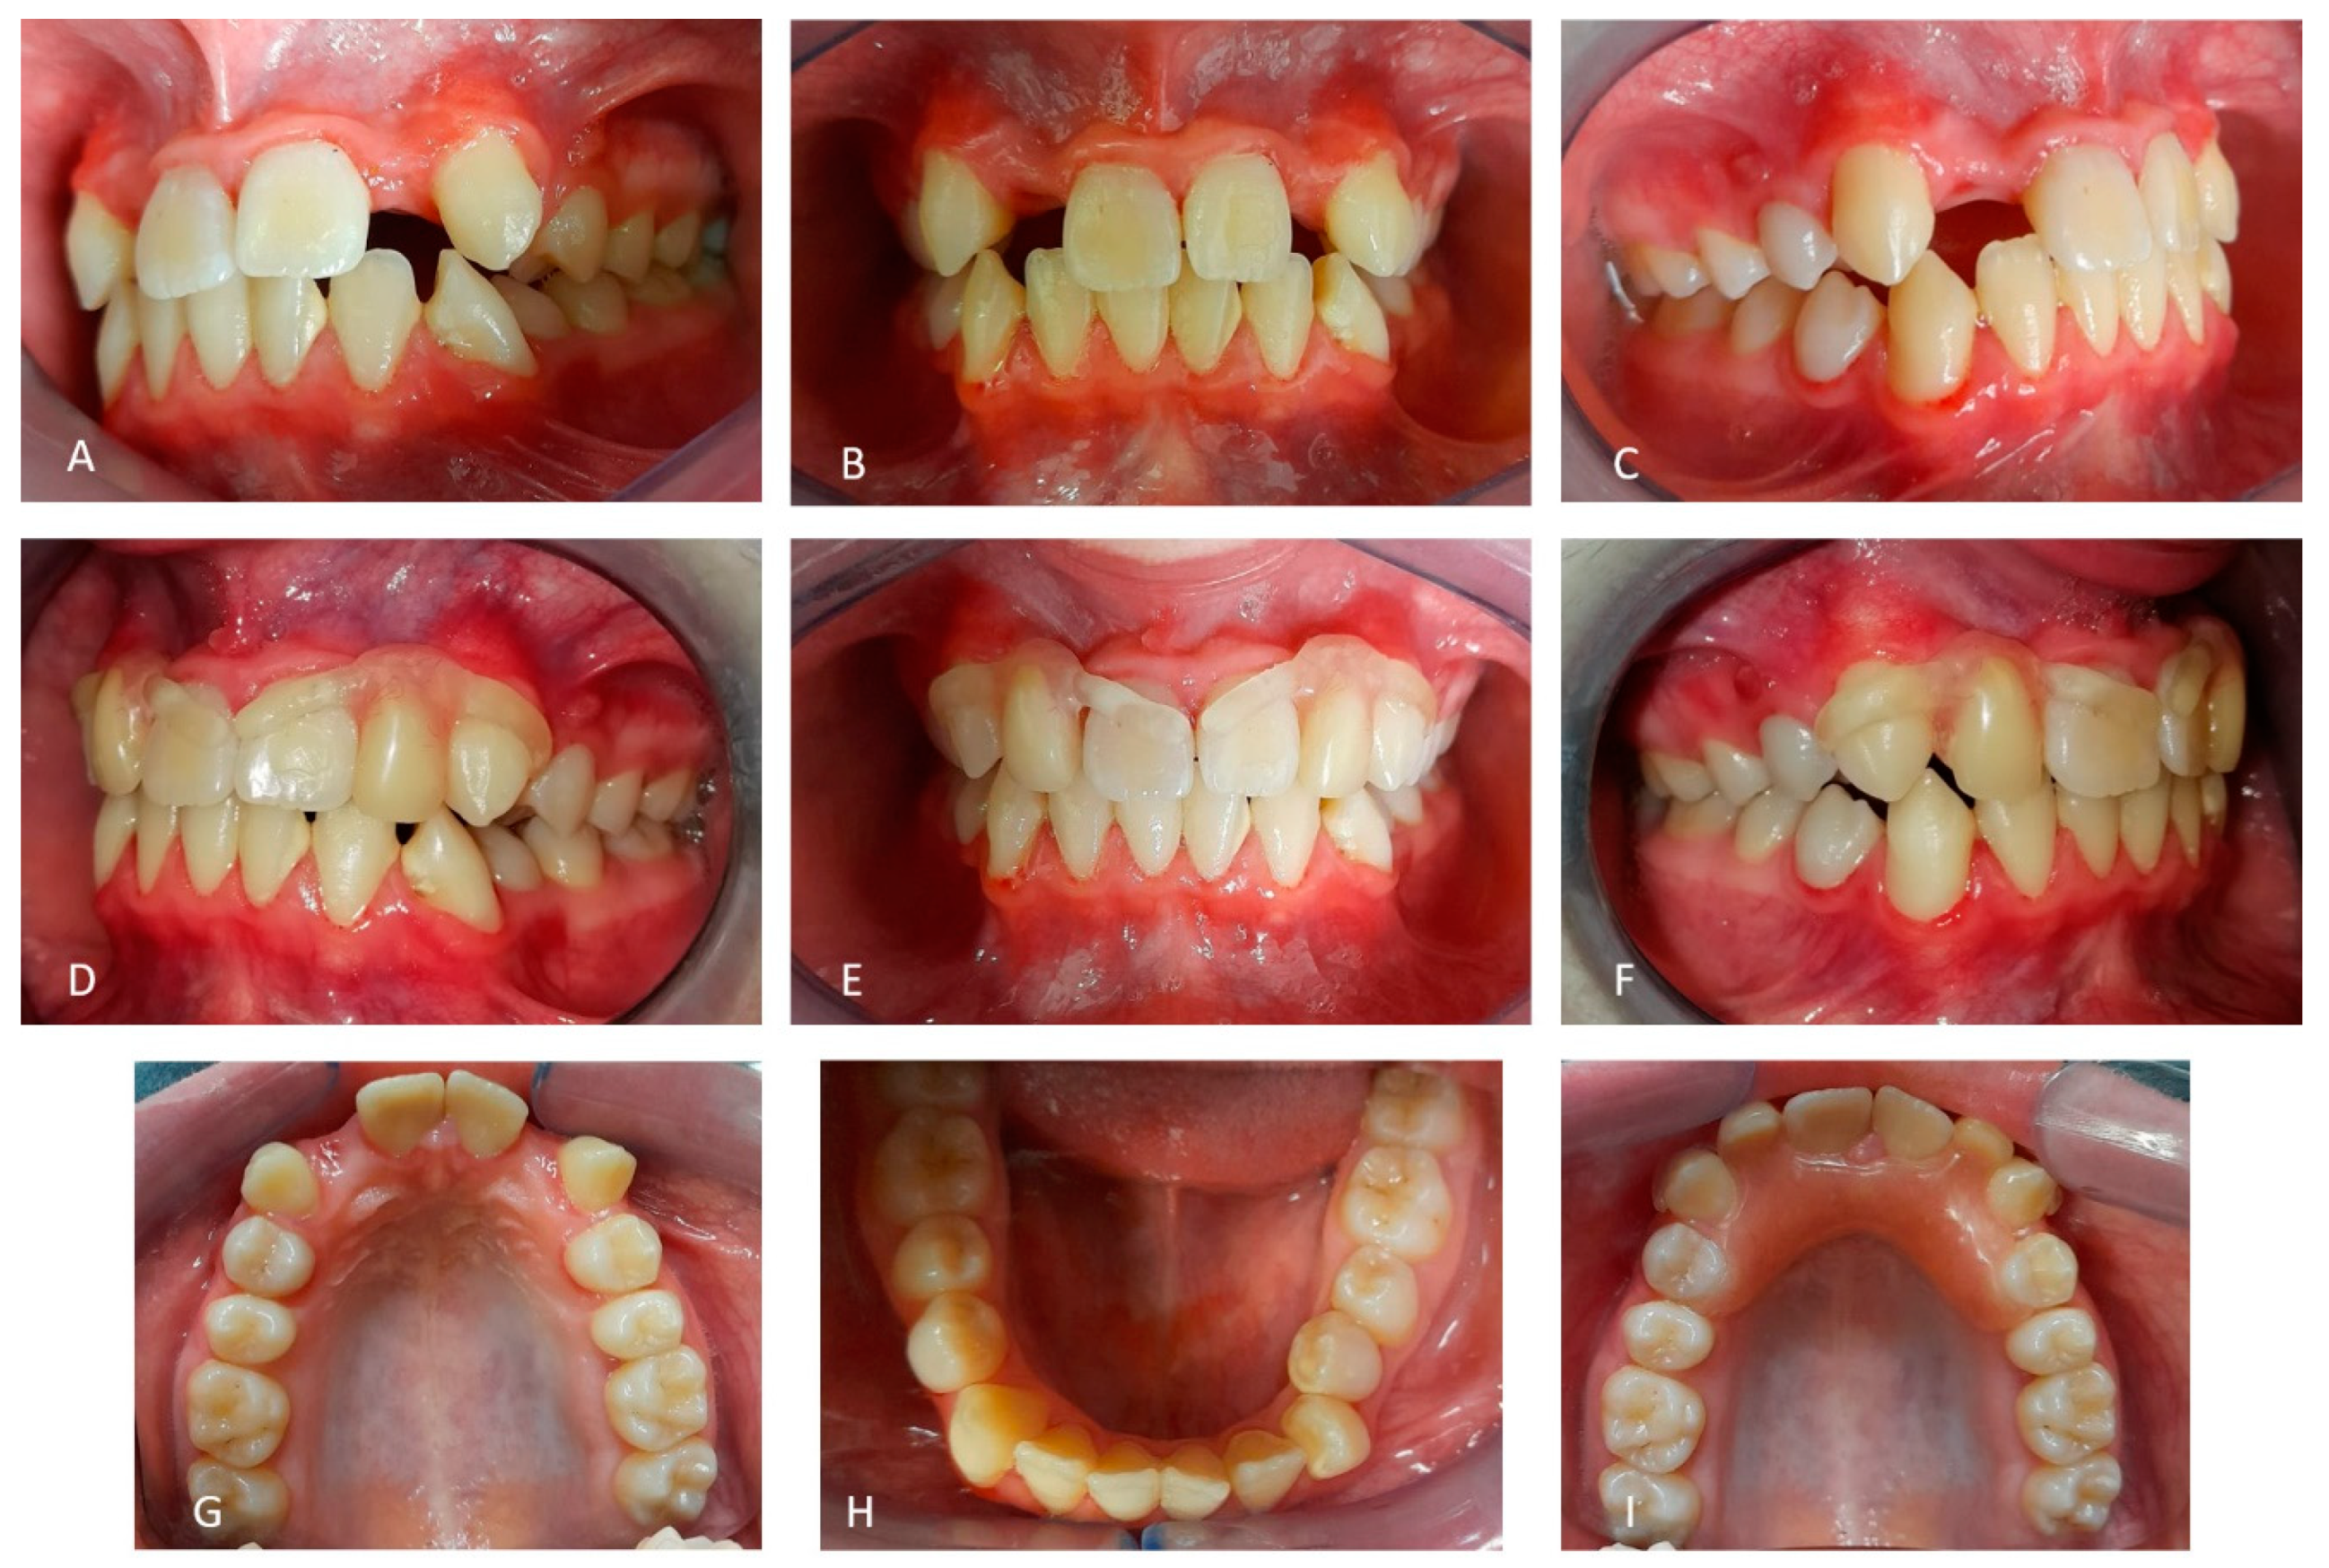

2.1. Patient A

2.2. Patient B